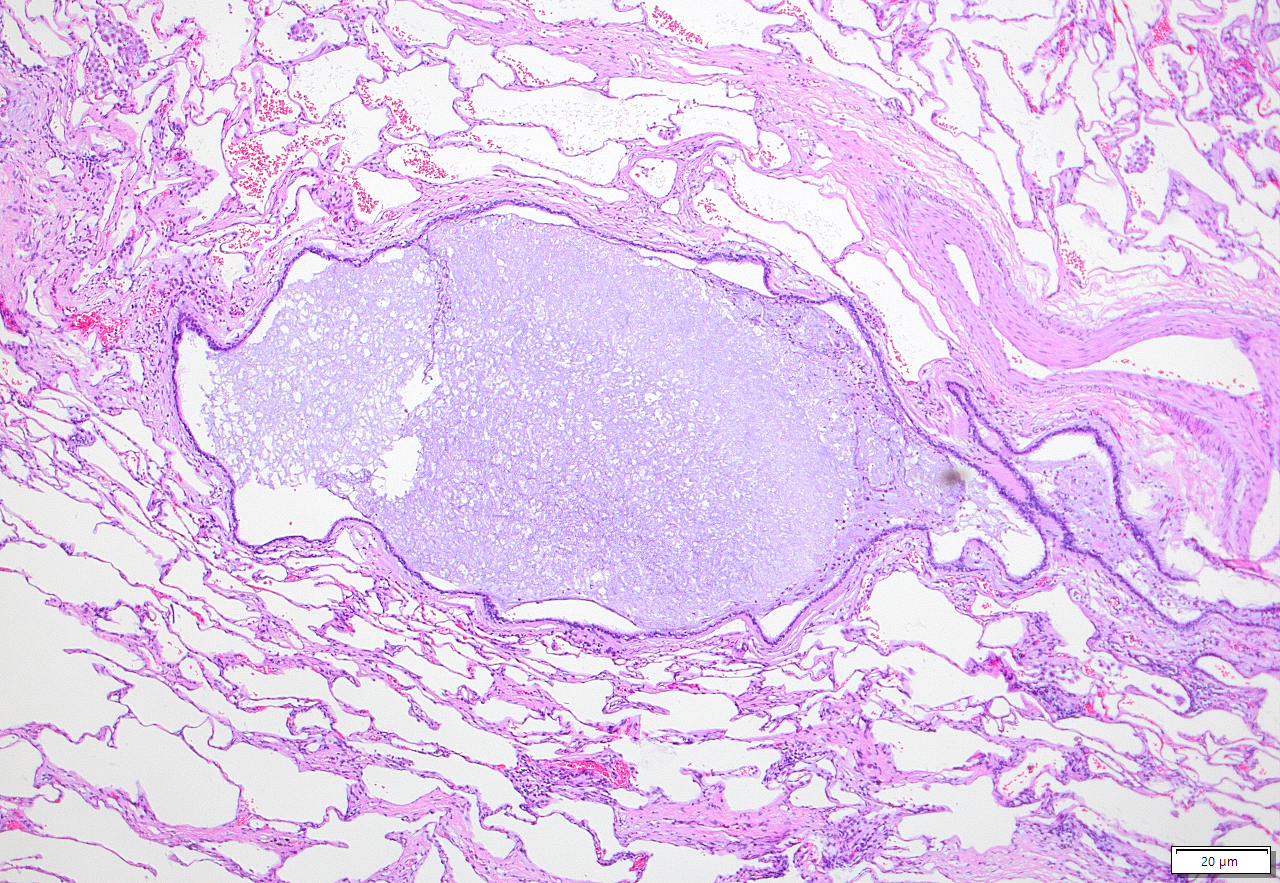

Dies ist ein ziemlich exemplarisches Aspergillom (leider habe ich keine Bilder vom Präparat, wer wissen will wie sowas aussieht: Wikipedia).

Ein Aspergillom ist gekennzeichnet durch (zunächst) nicht invasives Wachstum der Pilze. Hier in einem erweiterten Atemweg. Durch den dauernden Entzündungsreiz kommt es zu einer destruktion der lunge (im Bereich links ist nur noch Narbe, oben ist Emphysem, die Alveolarsepten "Lungenbläschen" sind also schon ziemlich kaputt).

1. Übersichtsbild. 1/4 der aufgeweiteten Bronchiektase (Erweiterter Atemweg) mit umliegender vernarbter Lunge